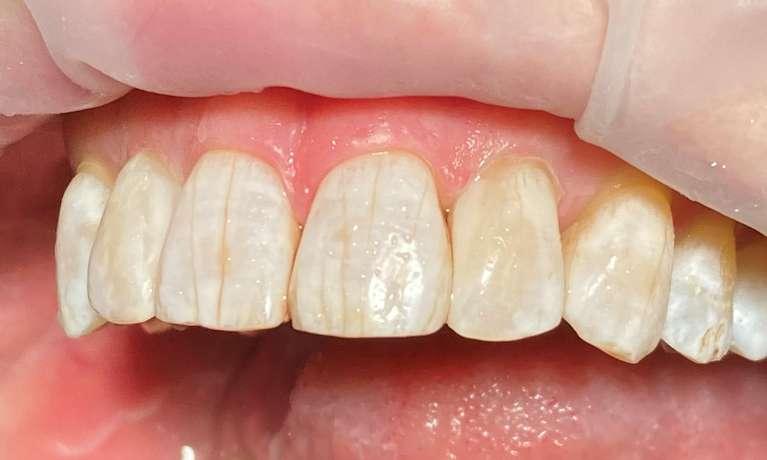

After braces, this patient had white spots around where the brackets had been. We use a resin infiltration called Icon that does not require any shots or drilling to remove these spots and harden the tooth structure! Visits take about 10 minutes per tooth and results are long-lasting.